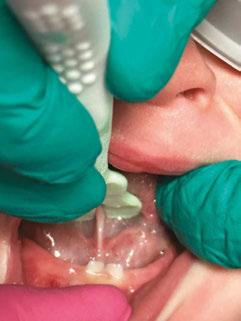

The 5-year-old patient featured in this case study did not benefit from early oral care and had multiple carious lesions. Considering the young age, high caries risk, and the uncertainty of compliance with follow-up appointments, I wanted to restore and seal all teeth in one visit. One quadrant is shown in this case study. The carious lesion on tooth J (65) was cavitated and prepared, restored, and sealed. Tooth I (64) was non-carious and would only be sealed (Figure 1).

I chose Activa™ Kids Bioactive-Restorative and Activa Presto (Pulpdent) as restorative materials for this case because I have seen excellent clinical results over time with these bioactive materials. Continuous release and recharge of calcium, fluoride, and phosphate from these restoratives are beneficial in the fight against decay long into the future.

Choosing restoratives based on ease of use and the ability to work quickly was important in this case. All restorations were completed under general anesthesia in one appointment. There were wear facets on the occlusal surfaces of the molars, so it was important to use a material that would have some flexibility and resistance to fracture. The innovative composition of Activa Kids includes an elastomeric monomer or “rubberized” component that absorbs forces and was an ideal filling material. Activa Presto shares similar properties, and it was convenient to use as an occlusal surface sealant for this patient.

Tooth J (65) was prepared with a coarse tapered high-speed diamond bur allowing for some minor mechanical retention by incorporating minimal undercut in preparation. The occlusal

surface of tooth I (64) was also lightly abraded with a diamond bur (Figure 2). The preparations were selectively etched with phosphoric acid, rinsed, and lightly dried (Figure 3). Bonding agent was applied to the entire occlusal surfaces of both teeth, air thinned, and light-cured (Figure 4).

Tooth J (65) was bulk-filled with Activa Kids. For this fast injection technique, I place the dispensing tip at the floor of the preparation and extrude the material without removing the tip until the preparation is completely filled (Figure 5). I like to do some minor manipulation of the filling material with hand instruments to create anatomy, as well as to ensure the material is flush with the surface of the preparation, and no air is trapped inside. Activa Kids is dual-cure, ideal for bulk filling, and can be cured with all lights. A thin topcoat of Activa Presto was placed as a sealant on the entire occlusal surface of teeth I and J (64 and 65) (Figure 6). Figure 7 shows the final clinical situation.

Figure 1 (left): Caries lesion on tooth J (65). Figure 2 (center): Preparation of tooth J (65) and abraded occlusal surface of tooth I (64). Figure 3 (right): Selective etch of enamel Figure 4 (left): Bonding agent is applied to both teeth I and J (64 and 65). Figure 5 (right): The preparation is filled with ACTIVA Kids Figure 6 (left): A thin topcoat of ACTIVA Presto is applied to the occlusal surfaces of teeth I and J (64, 65). Figure 7 (right): Final result